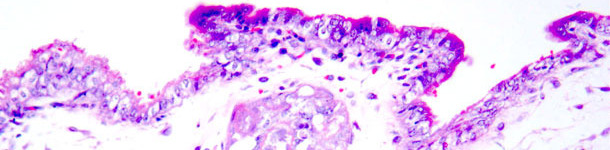

Parmi ex les grandes lignes de la recherche où il a participé on trouve Mycoplasma hyopneumoniae, le virus Aujeszky, le virus de l'hépatite E, le virus torque teno et les maladies associées au circovirus porcin de type 2 (PCV2). Dans ce dernier domaine il se concentre sur la pathologie de la reproduction du PCV2 dans des modèles expérimentaux (infection par du sperme contaminé par PCV2 chez les nullipares vaccinées et non vaccinées contre le PCV2 pour détecter les troubles de reproduction et les dommages embryonnaires / fœtaux.